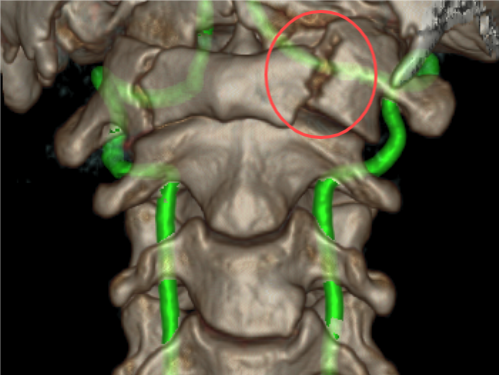

近日,重庆医科大学附属璧山医院(重庆市璧山区人民医院)神经外科成功为一名遭遇严重寰椎骨折的患者施行了高难度的后入路寰椎骨折复位内固定术以及枕颈融合植骨固定术,术后随访显示,患者恢复状况良好,拥抱健康新生活。